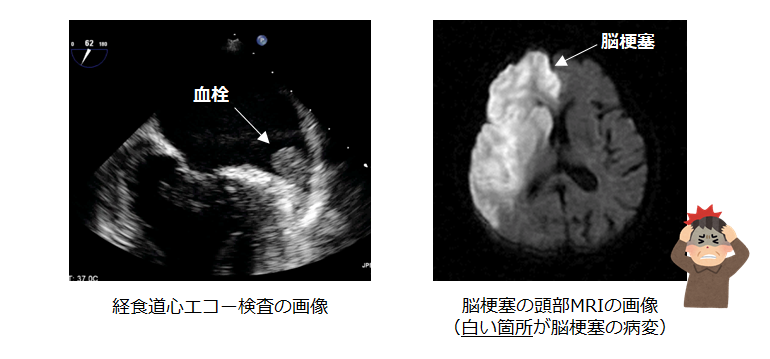

心臓の中における血流が滞ることによって血栓(血のかたまり)が形成されます。

それが全身に飛ぶことによって様々な塞栓症を引き起こします。特に重大なのが脳梗塞で、もともと血圧が高い方や糖尿病をお持ちの方、75歳以上の方が発症しやすいと言われています(※)。また心房細動が原因で発症する脳梗塞は他の原因よりも重症化することが 知られています。(下記はいずれも当院実施の検査画像)

※ Ann Intern Med 2009;151:297–305